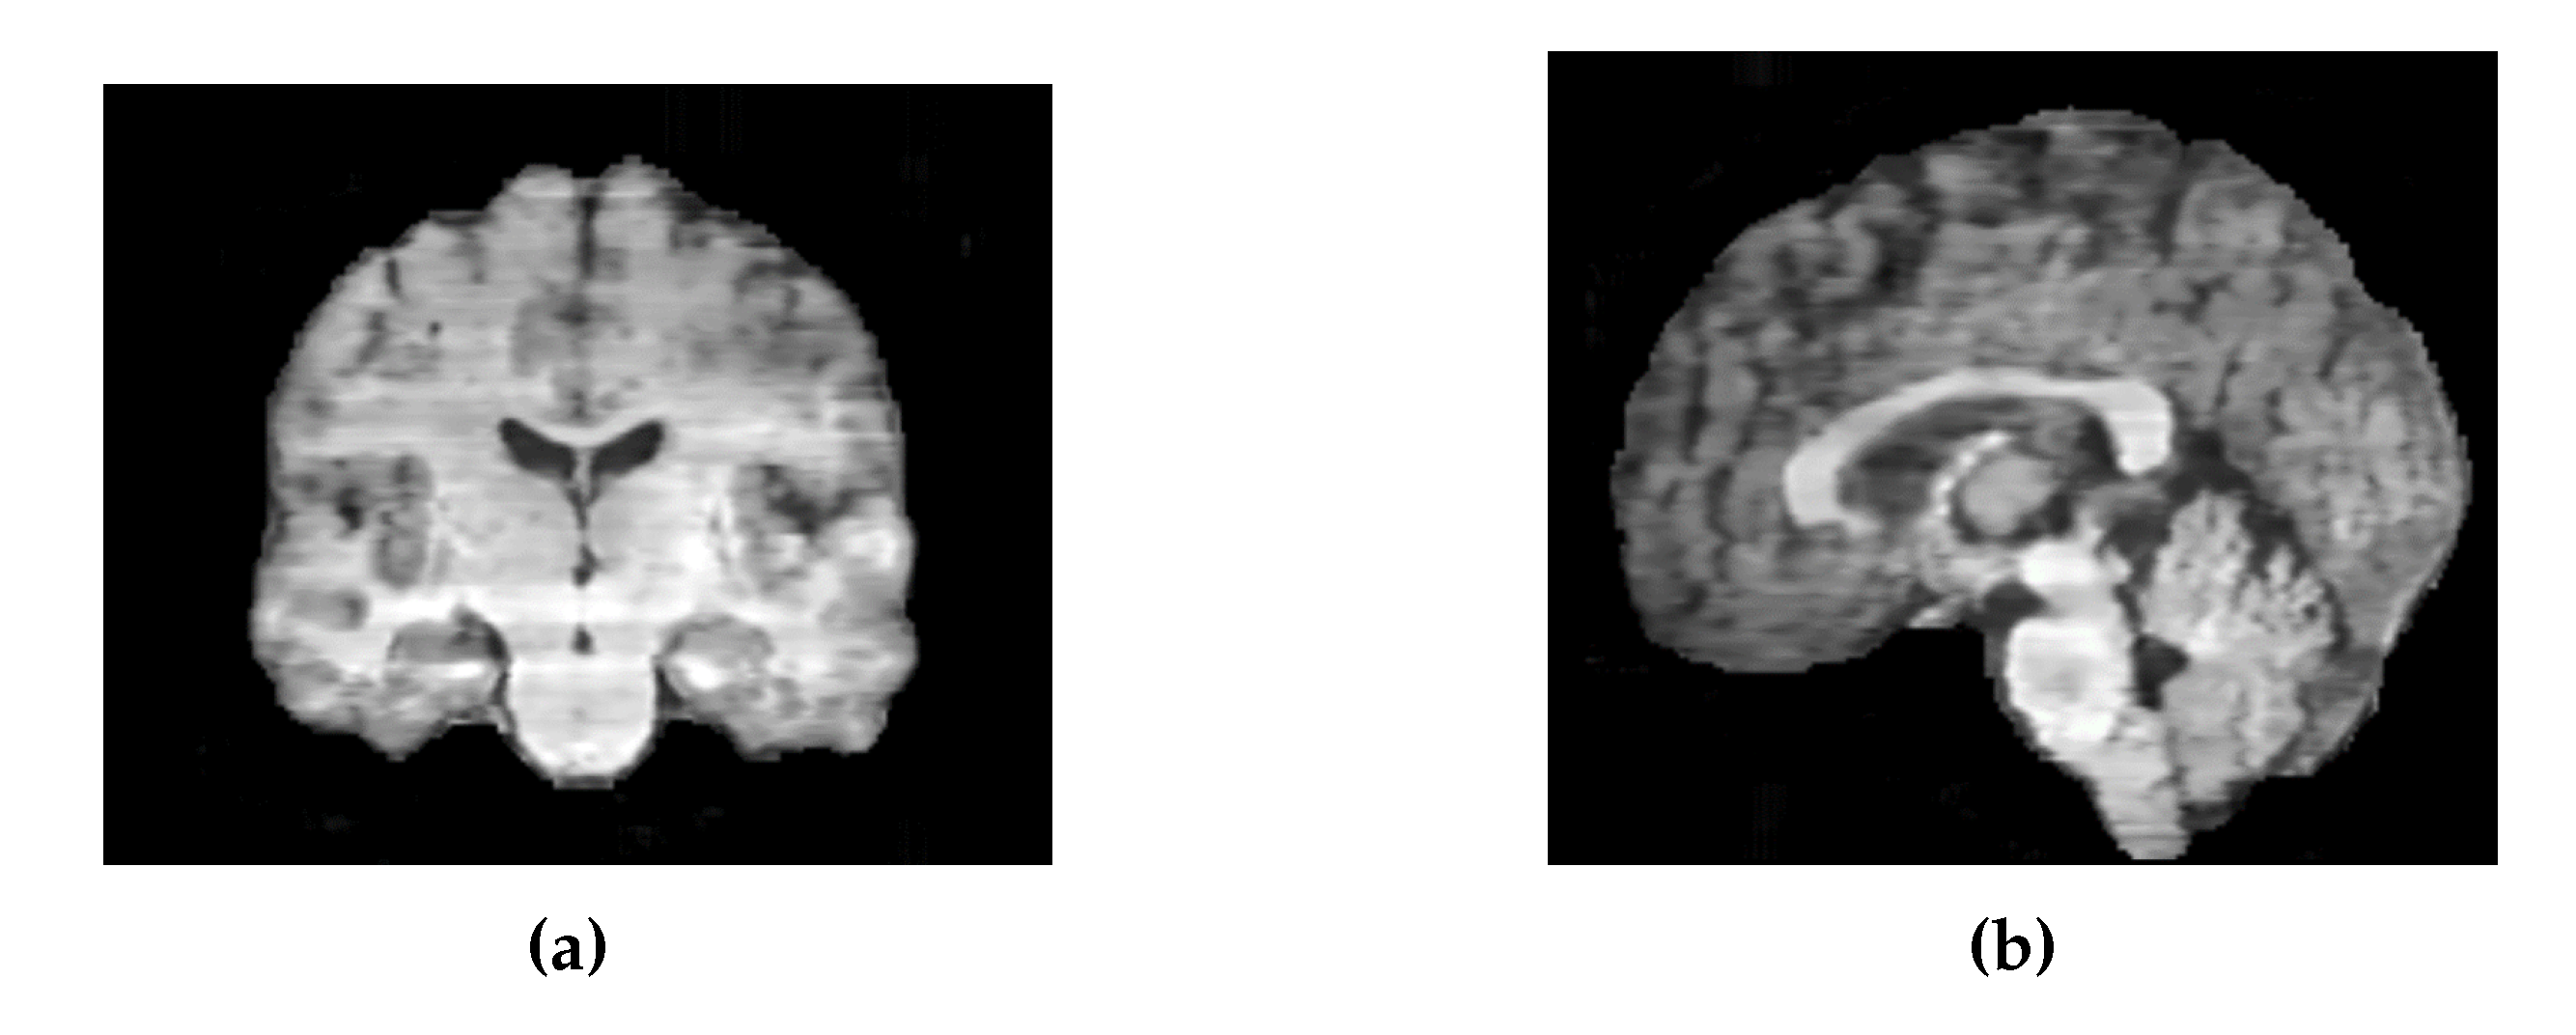

Similarly, the images generated by the 2D UNet model exhibited intensity variations between slices along the sagittal and coronal axes (Figure 24). To address this, it would be preferable to train the model on axial, coronal, and sagittal slices, and then average the results across all three dimensions.

Figure 24. (a) Coronal slices of an MRI generated by 2D UNet. (b) Sagittal slices of an MRI generated by 2D UNet.